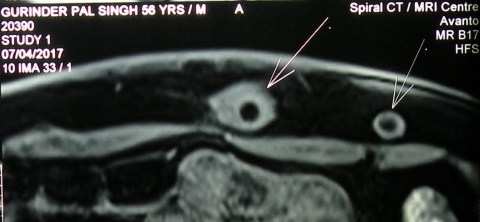

12.3.18

A presumed abscess of the thigh ( huge in size, diagnosed clinically and confirmed on CT scan) drained in an elderly ( 60 years old) female. The fluid was largely serous with lots of flakes. When examined after a month or so, the wound had partially healed but the cavity was filling up with a fleshy growth. Was referred to PGI where a high-grade soft-tissue sarcoma was diagnosed. She died soon after.